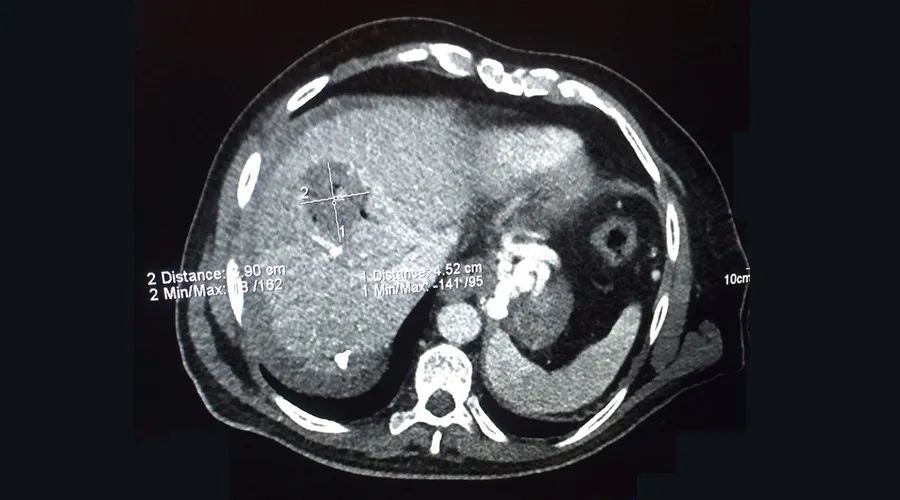

术中影像资料

两例肝脏消融中,其中一例的肿瘤大小 为2.5cm×2.7cm。主刀医生使用赛诺微SS-MWA-1531C微波天线,单针消融十分钟(100w,10min)。得益于Elia Coimbra教授专业的经皮穿刺技术以及Dophi™ M150E微波消融系统安全可靠的性能,手术成功完成。尤其是赛诺微微波消融天线的全天线(水冷直至针尖)水冷设计,精准的能量输出能力,让微波消融克服了市面常规微波设备不可控的技术弊端,完成了对于肿瘤的精准消融。